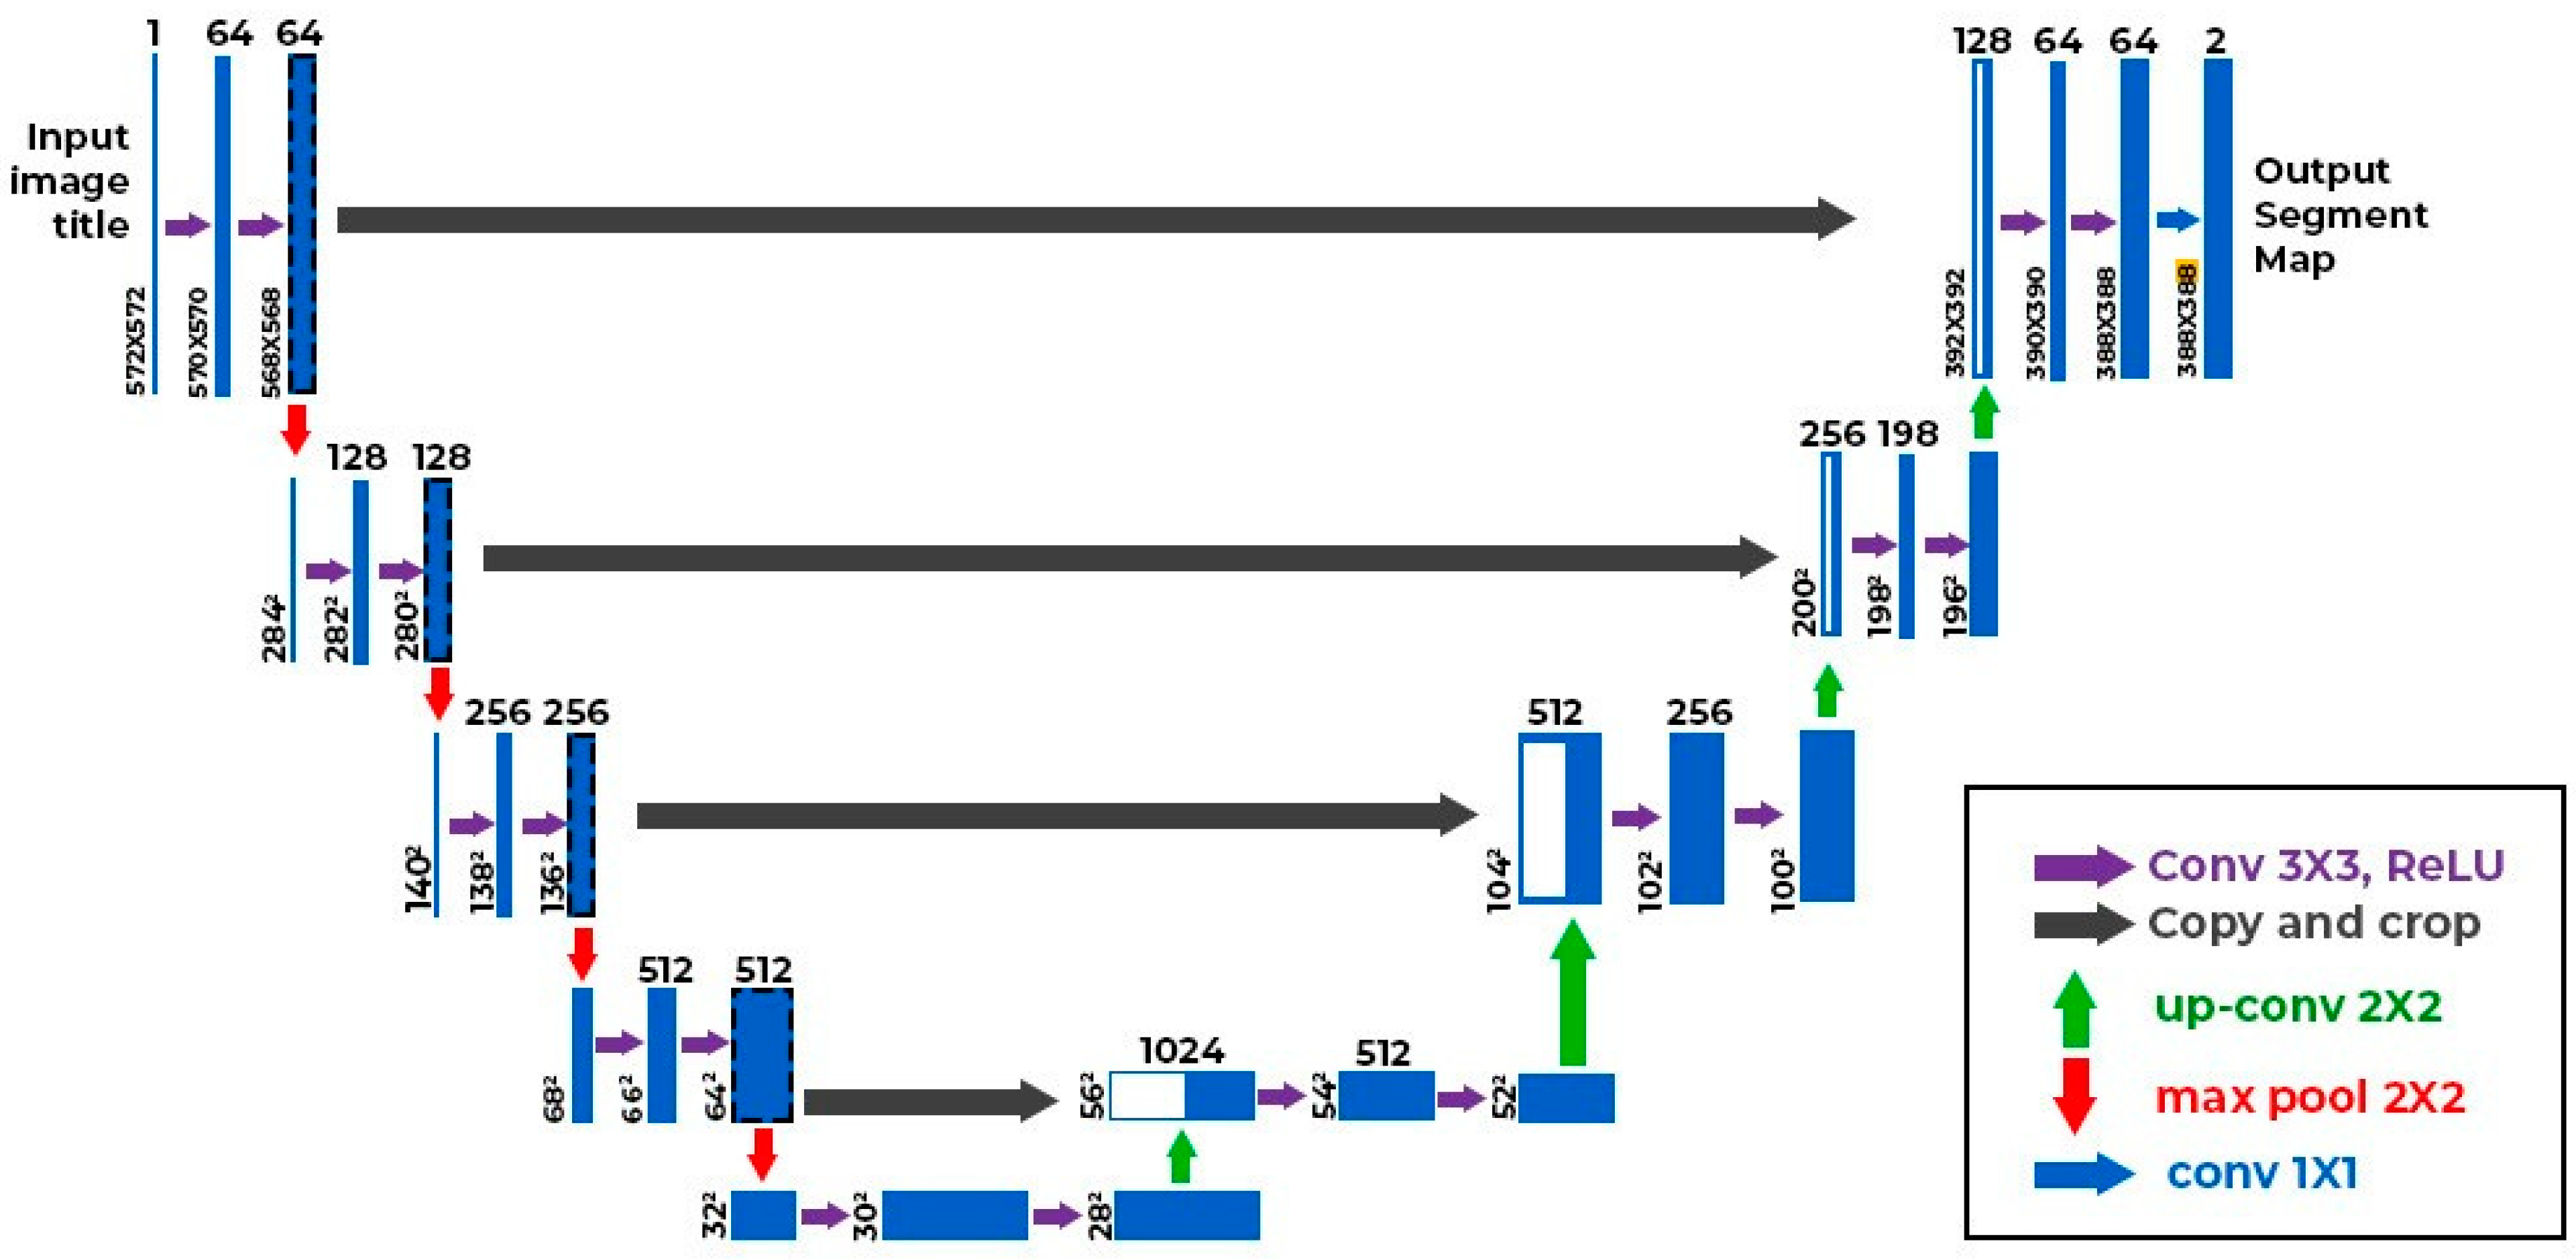

2.3. AI Algorithm